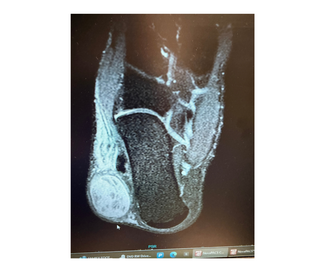

Vibrio vulnificus necrotizing fasciitis is a rapidly progressive, often fatal soft tissue infection that demands immediate clinical recognition and decisive surgical management. This case underscores the limitations of relying on the LRINEC...